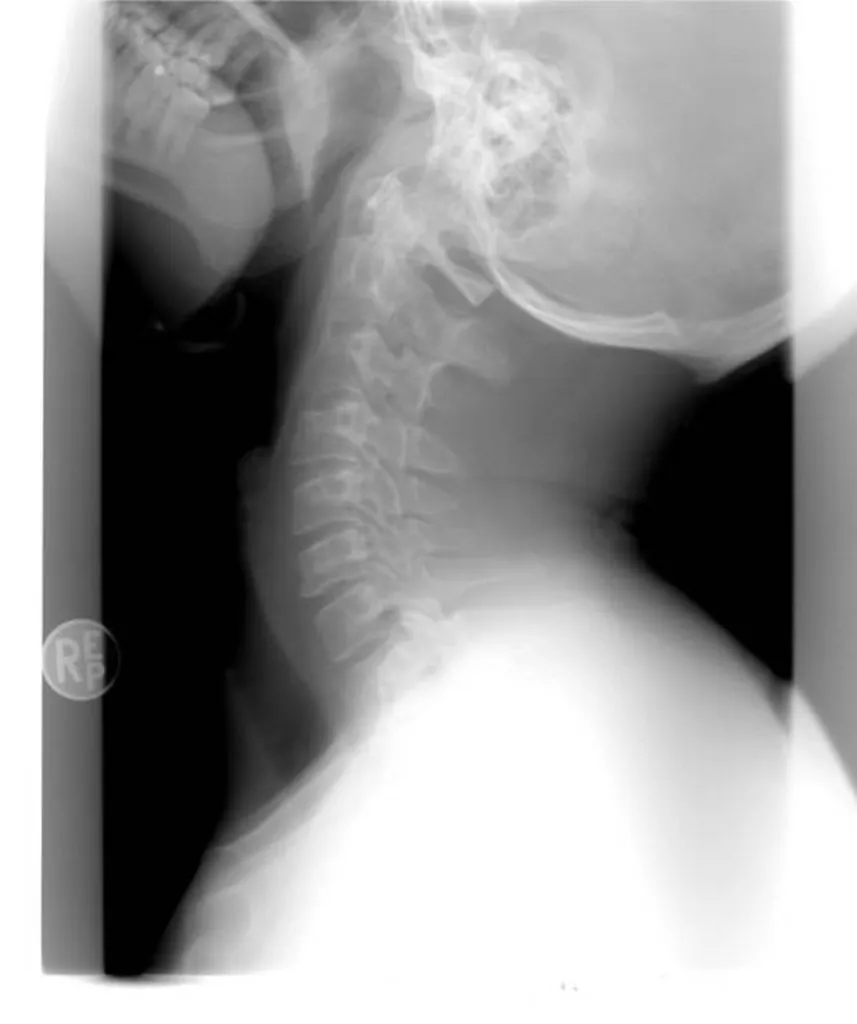

avocat de victime d’accident de la route en voiture, ayant subi un coup du lapin à Marseille

Montants d’indemnisation du dommage corporel de victimes d’accident de la route en voiture subissant un coup du lapin cervical lors d’un choc arrière selon notre cabinet d’avocat à Marseille

La victime d’accident de la route subissant un coup du lapin ou entorse cervicale lors d'un choc arrière en voiture sur l’autoroute à Marseille, a droit à l’indemnisation de son dommage corporel, sur le fondement de la loi du 5 juillet 1985, dite aussi loi Badinter. Ce type d’accident entraîne en...

Avocats de victimes d’accident de la route en voiture à Toulon ayant subi un coup du lapin.

11 628 euros alloués à une victime d’accident de la route en voiture à Toulon ayant subi un coup du lapin en réparation de son dommage corporel par l’intermédiaire de notre cabinet d’avocats

Par procès-verbal de transaction du 8 février dernier, notre cabinet d’avocats a obtenu la somme de 11.628 € à titre d’indemnisation du dommage corporel d’une victime d’accident de la route en voiture à Toulon, ayant subi un coup du lapin. La victime souffrait, depuis l’accident de la circulation ...

Avocat pour l'indemnisation d'une entorse cervicale en cas d'accident de la route à Marseille

16 918 € d’indemnisation versées à un chauffeur VTC victime d’accident de la route, ayant subi une entorse cervicale à Marseille

Notre Cabinet a obtenu le versement de la somme de 16 918 € à titre de dommages intérêts en indemnisation du préjudice corporel d’un chauffeur VTC ayant subi un accident de la route à Marseille, précisément un choc arrière, entrainant une entorse cervicale.L’indemnisation du dommage corporelle de ...

15 037 € de dommages intérêts alloués à une victime d’accident de la route conducteur, ayant subi une entorse cervicale à Marseille.

15 037 € de dommages intérêts alloués à une victime d’accident de la route conducteur de voiture, ayant subi une entorse cervicale à Marseille.

Le conducteur de voiture victime d'accident d'accident de la route à Marseille ayant subi une entorse cervicale a droit à l'indemnisation de son dommage corporel, sur le fondement de la loi du 5 juillet 1985, dès lors qu'il n'a pas commis de faute de conduite.Notre cabinet d’avocat a obtenu réce...